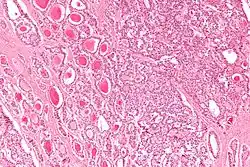

| Micrograph of a strumal carcinoid. H&E stain. |

The strumal carcinoid is a type of monodermal teratoma with histomorphologic features of (1) the thyroid gland and (2) a neuroendocrine tumour (carcinoid).[1][2]